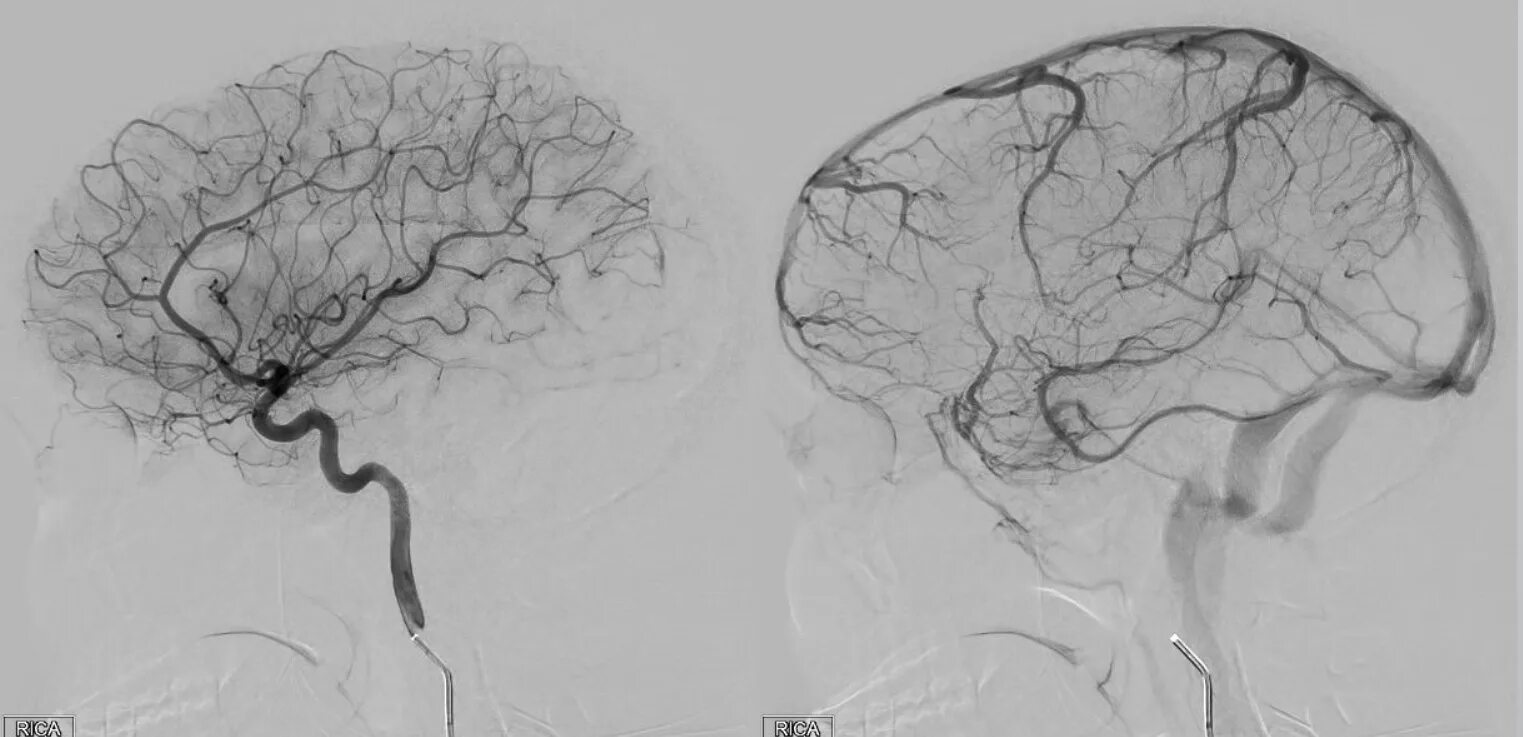

Эмболизация гемангиомы